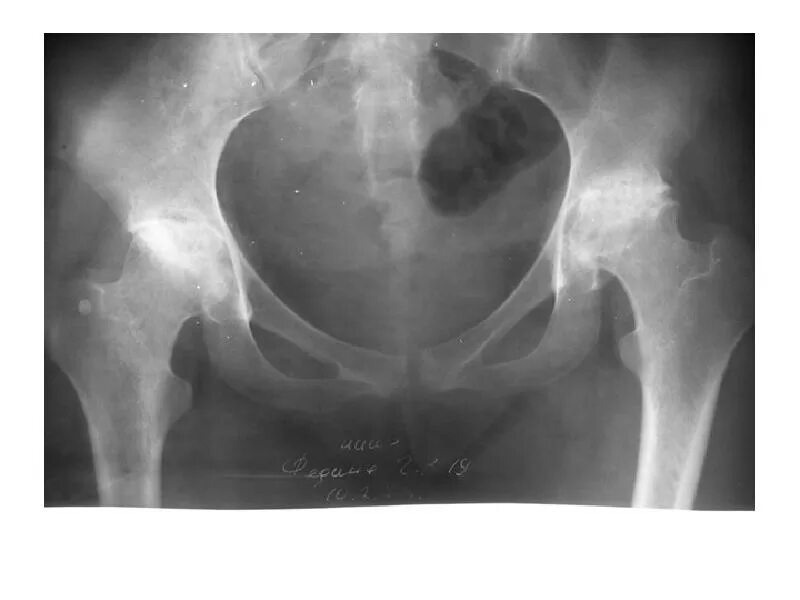

Асептический некроз инвалидность